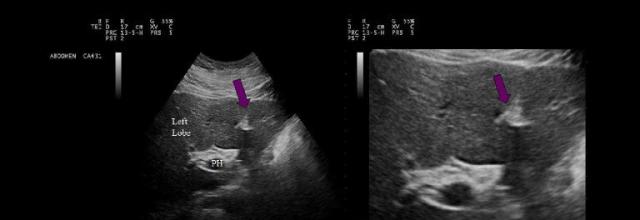

The purple arrows point to which of the following liver structures?

ligamentum teres |